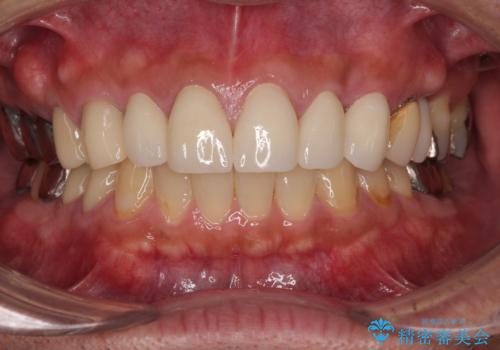

右上側切歯に対して根管治療を行い、その後右上側切歯から左上犬歯まで計5本をオールセラミッククラウンで補綴する治療計画をご提案しました。

- 75万円(税込)費用は治療当時の料金となります